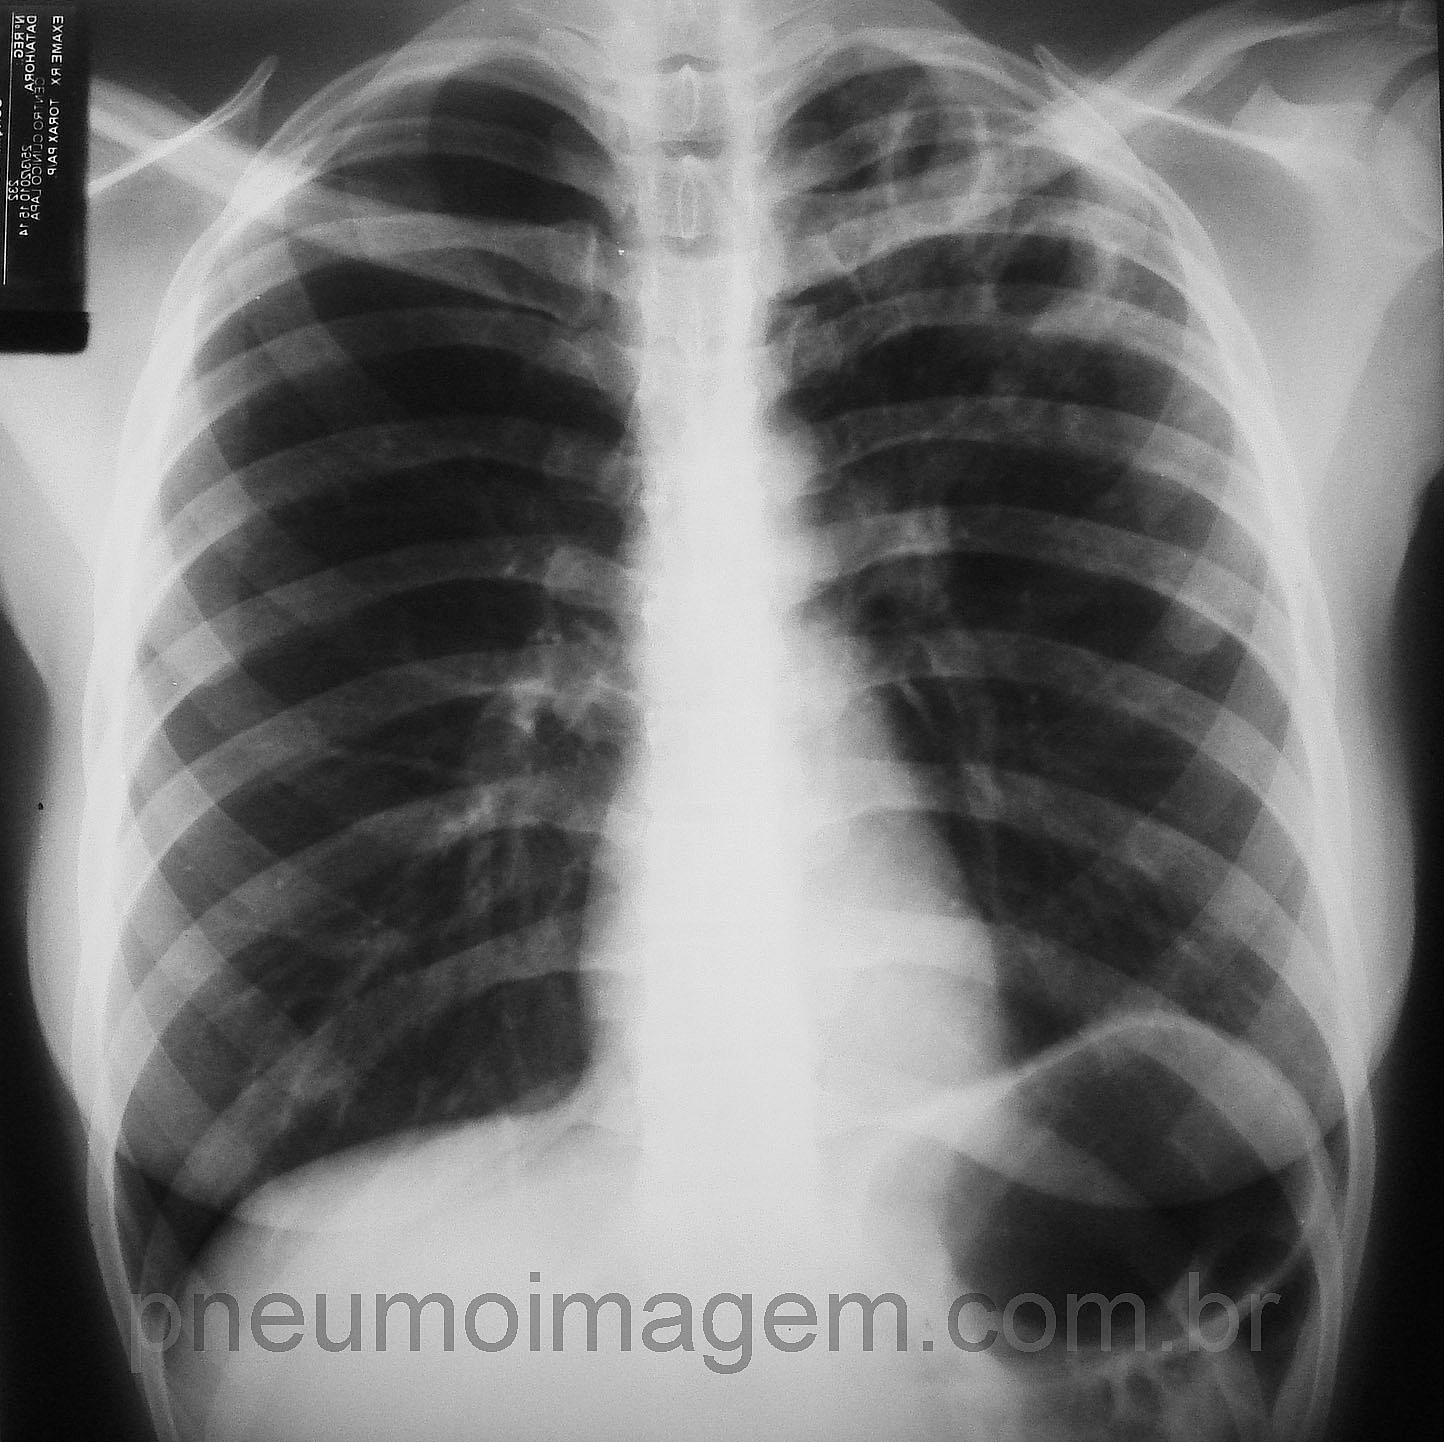

CASO CLÍNICO #26

CASO CLÍNICO #26Paciente com febre, emagrecimento e hemoptoicos. Qual o diagnóstico mais provável? Deixe os seus comentários abaixo.

Patient with fever, weight loss and hemoptysis. What is the most probable diagnosis? Write your comments below.

Tuberculose Pulmonar